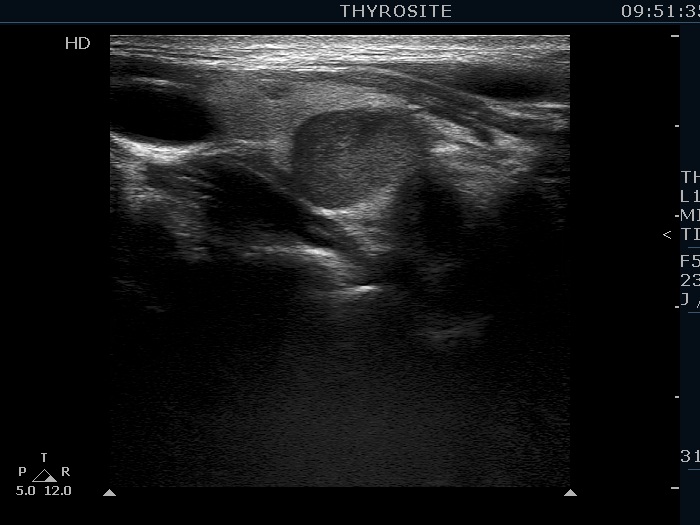

Clinical data: A 43-year-old woman was diagnosed with primary hyperparathyroidism. Scintigraphy disclosed an enlarged right lower parathyroid. The initial cause of evaluation was elevated serum calcium level detected by chance. The patient was referred in order to confirm and to accurately localize the lesion before surgery.

Ultrasonography. The thyroid was echonormal. There was a hypoechoic mass within the lower pole of the right lobe. The lesion was surrounded by thyroid tissue throughout.

Ultrasound-guided aspiration cytology resulted in benign lesion.

Additional tests: wash-out parathormone 769 pg/mL, wash-out thyroglobulin 0 ng/mL.